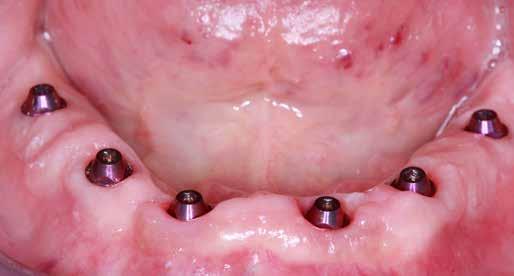

Az európai uniós rendeletekkel való harmonizáció keretében új szakvizsgák, feltételek, követelményrendszer alakult ki a hazai sztomatológiában. Megjelent az új orális implantológia szakvizsga, és egészen új szintre került a többi fogászati szakorvosi vizsga követelményrendszere is. Az új szakvizsgákhoz tartozó követelmények egyben a szakma új szabályainak is tekinthetőek, vagyis jelentős feladat elé állítják a rendelőket. A fejlődést a páciensek is nyomon követhetik az interneten keresztül, és ezzel új, és a réginél sokkal magasabb igényszintű fogászatot, implantológiát elvárásként fogalmazhatják meg. Ha ezt az új színvonalat, a fejlődést kevéssé követő fogorvosi rendelővel szemben várják el, akkor az ott végzett kezelések után kialakulhat a „konfliktus szituáció.” (1–3. képek)

Két évtizeddel ezelőtt a 60 év felettiek jellemző módon főként alsó és felső teljes fogsort, kivehető protézist kívántak. Többségük közepesen informált volt, 60-70 százalékuk vett rendszeresen igénybe valamilyen fogászati ellátást. Most a magánorvosi ellátás irányába tolódott el a rendszer, még a 75 év felettiek is gyakran implantátumot szeretnének, 20%-uk rendkívül informált, az internetről tájékozódik.

Az implantológiában inkább a szájsebészeti jellegű témák voltak hangsúlyosak, a manuális eljárások dominanciája volt jellemző. Ma inkább a különleges csontpótlásokról, az előre megtervezett fogpótlásból (backwards planning = visszafelé tervezés) kiindult sebészeti tervezésről esik sok szó, ez vált követelménnyé. A digitális eljárások fölénybe kerültek a manuálisokkal szemben. A régi technológiák folyamatosan kikopnak a gyakorlatból. És itt is kérdés: Mi az, ami megfelel – még vagy már – a szakma szabályainak? Már csak emiatt is sok mindent újra kell gondolni (4–5. képek)